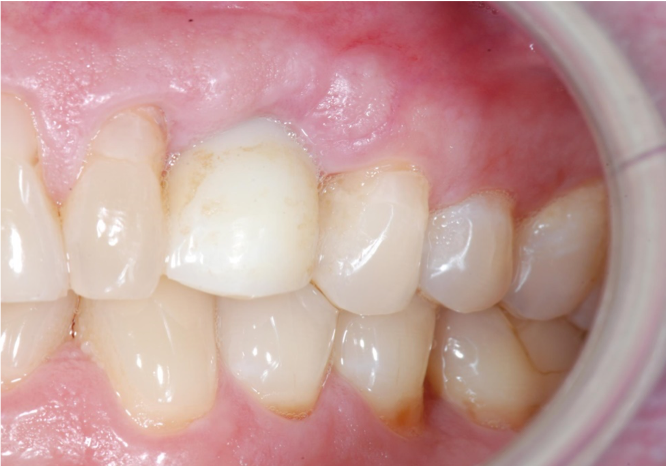

The first case involved a 45-year-old man presenting with the complaint that his dentist told him they could not put a tooth on his implant. He was also unhappy with an implant that was placed too supragingivally. The healing cap was in contact with the distal tooth. The implant was not restorable in the position it was placed (Figure 3). If the patient were willing to undergo orthodontics, there may have been a chance to place a tooth on the implant. In the end, though, no matter what the clinician was able to place or how the adjacent teeth were modified, the result would not be optimal.

Fig 3. Non-restorable implant that would have benefited from collaboration earlier.

Figure 3